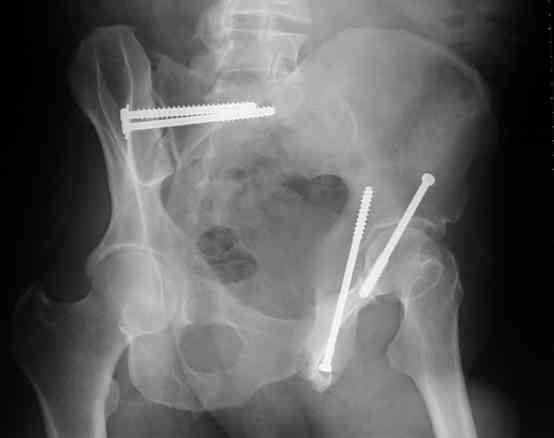

I'll include a few images of a similar injury in a similarly large male patient. This patient "showed up" in our ER c/o hip pain 2 months after being treated in the lateral position, without a quality reduction, without an anterior column transverse supporting implant, with an unbalanced plate applied too medially, with insufficient caudal segment fixation...it took over 8 hours and a 3+ l blood loss to debride the callus from front then

back, excise the HO, release his sciatic nerve, reduce the head-transverse-wall, and fix it...and now it's a staging procedure.

The 2nd example is of a motorcyclist with a transverse fracture-dislocation...he had a closed attempted reduction and placed in traction but the manipulative reduction was not concentric (not unusual for this injury pattern)...so the traction was adjusted to be just enough to disengage the head from the fracture (12#) until he could be cleared for surgery one day after injury...he was treated "urgently" then with a prone KL, clean the fracture, reduce and clamp it, screw it, support with a balanced plate, close, and enjoy...2-3hours, 400cc EBL, blah, blah, blah..